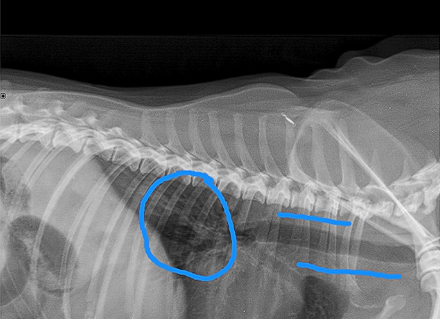

Little area of consolidation but nothing else significant

DX - chronic cough suspicions for airaway disease due to chronic unproductive cough

On left hand side (actually right ariway) airway is compressed

Wouldn’t be ablse to see mass on radiograph as heart borders block ti

Bronchoscopy - wouldn’t be able to see the mass - only see the collapse but not what caused it

CT is our bitch